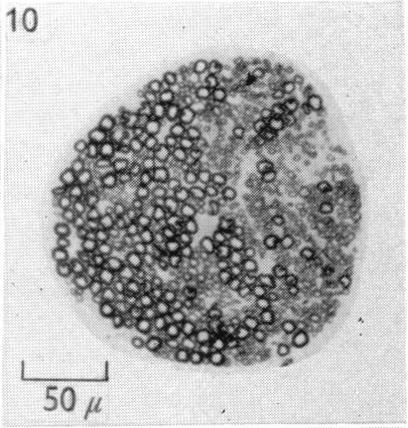

Functional and histological studies of the vagus nerve and its branches to the heart, lungs and abdominal viscera in the cat.

J Physiol. 1957 Jan 23;135(1):182-205. doi: 10.1113/jphysiol.1957.sp005703.